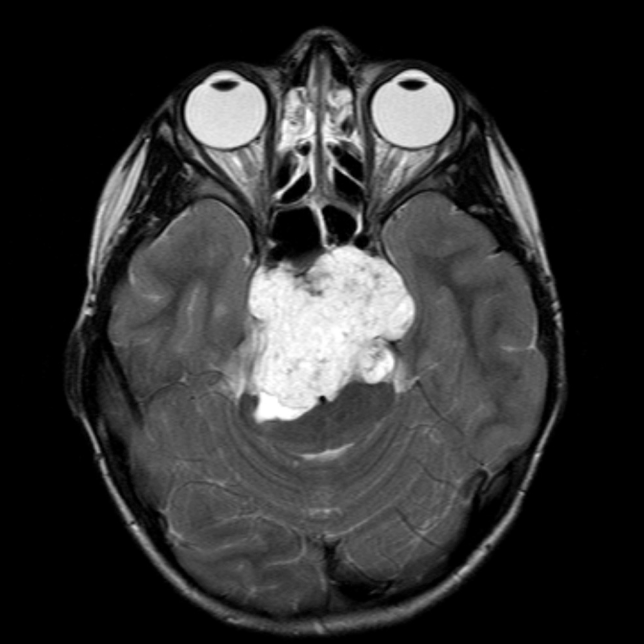

脊索瘤的较新治疗方法是什么?经鼻入路内镜手术成功案例一则

脊索瘤的较新治疗方法是什么?经鼻入路内镜手

问:脊索瘤能完全治愈吗? 答:脊索瘤是发生在头盖骨和脊椎上的恶性肿瘤。这是一种少见的肿瘤,每年每100万人中就有1人会得,在颅底肿瘤中也很难治疗。肿瘤从头盖骨到神经...

头部 脊索瘤手术 痛苦吗?脊索瘤起源于脊索组织内的脊索细胞,约 30% 的脊索瘤发生于头部的中心,即颅底区域,也被称为颅内脊索瘤、脑脊索瘤。而头部脊索瘤的治疗一般都是优选手...

脊索瘤 是一种起源于胚胎脊索残余的局部侵袭性肿瘤。使用监测、流行病学和较终结果数据库的基于人群的研究表明,每106人脊索瘤发病率为8.4。尽管斜坡脊索瘤占全部脊索瘤的三分之...

脊索瘤 是少见的缓慢生长的恶性肿瘤,来源于脊索残余。它们出现在轴向骨骼的任何地方,但比较常见于骶尾部和枕骨区,脊索瘤是局部侵袭性的,具有低转移潜能;手术切除很少,解...

问:颅内脊索瘤早期症状,能治吗? 答:颅内脊索瘤早期症状 取决于肿瘤的大小和位置。肿瘤可引起麻木,背痛,头痛和视力问题等症状。 颅底的脊索瘤,也称为脊索瘤,可以影响面...

问:脊索瘤复发的评估因子有哪些? 答: 脊索瘤是脊索性起源的恶性肿瘤,通常出现在骶尾部,斜坡或脊柱中。颅底脊索瘤的处理特别具有挑战性,因为它们位于重要的解剖结构附近...

问:脊索瘤治疗新方法有哪些? 答: 脊索瘤是一种少见的癌症,发生在颅底和脊柱的骨骼中。脊索瘤占全部骨肿瘤的约3%,占原发性脊柱肿瘤的约20%。它们是骶骨和颈椎较常见的肿...

问:脊索瘤好发部位在哪里? 答 :脊索瘤是一种少见的癌性肿瘤的,可以在任何地方发生。沿脊柱,从头骨到尾骨发展。脊索瘤缓慢生长,逐渐延伸到周围的骨骼和软组织中。它们经...

脊索瘤 是一种局部侵袭性肿瘤,起源于胚胎脊索残余。使用监测,流行病学和较终结果数据库进行的基于人群的研究表明,脊索瘤发病率为每1000000人8.4例,中位生存期为7.7年。虽然斜...